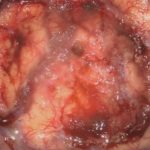

術中写真

摘出 前

摘出 中

摘出 後